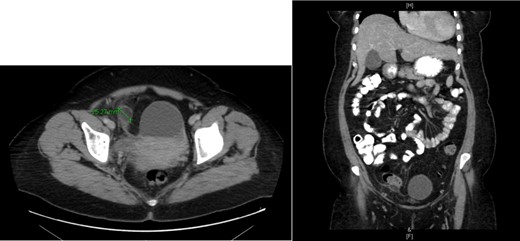

The patient was under the care of Obstetrics/Gynecology and due to persistent pain they elected to take her for emergency laparoscopy exploration. Intraoperative, general surgery team was consulted due to a gangrenous mass adherent to the right lower quadrant abdominal wall, originating from sigmoid colon. The small bowel was inspected from the duodenojejunal junction until the terminal ileum, which was healthy, the colon was inspected until reaching the gangrenous mass, adhesionlysis done and the mass separated from the abdominal wall (Fig. 2). The decision was to proceed for excision of the gangrenous sigmoid appendagitis and deroofing of left ovarian cyst. The postoperative period was uneventful. The histopathology result of specimen reveled necrotic adipose tissue. The ovarian cyst showed a serous cystadenoma.

A laparoscopic view of gangrenous sigmoid appendagitis after adhesiolysis from abdominal wall.